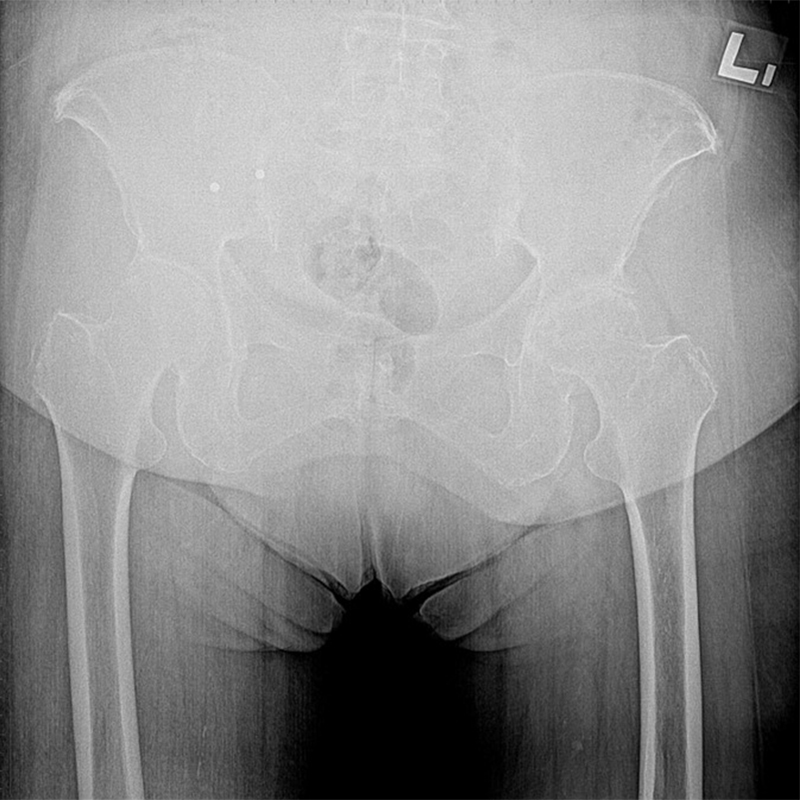

機器手臂手術 首頁 案例分享 髖關節手術 機器手臂手術 72歲 楊女士 退化性關節炎 術前 術後 60歲 彭先生骨股頭壞死 術前 術後 53歲 王女士退化性關節炎(DDH先天發育不全 CROWE TYPE 2) 術前 術後 83歲林女士退化性關節炎 術前 術後 83歲林女士退化性關節炎 術前 術後 楊女士 70歲 術前 術後 蔡女士 60歲 術前 術後